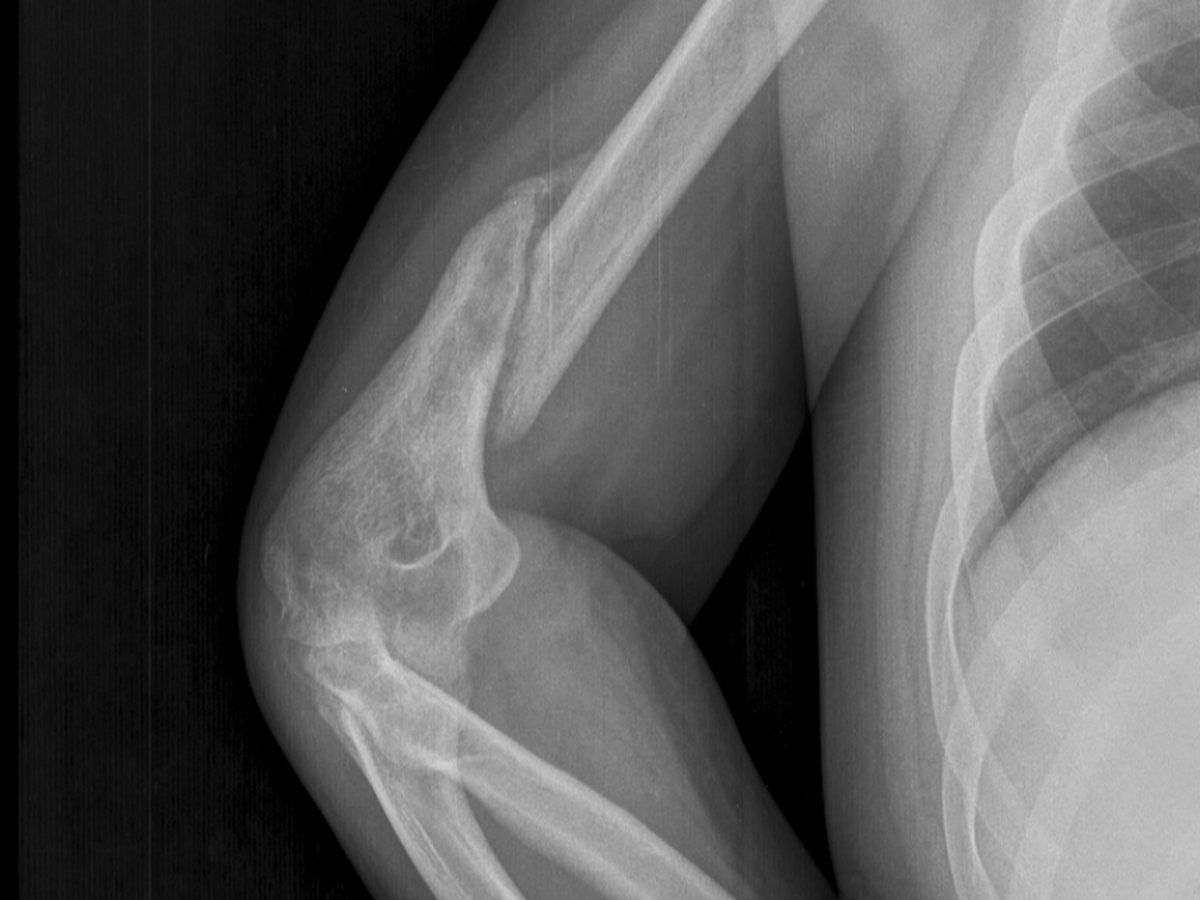

Diego Alejandro Parra Salas, es un joven zuliano que tuvo un accidente y sufrió una fractura de su brazo hace 4 meses, y necesita ser operado con urgencia.